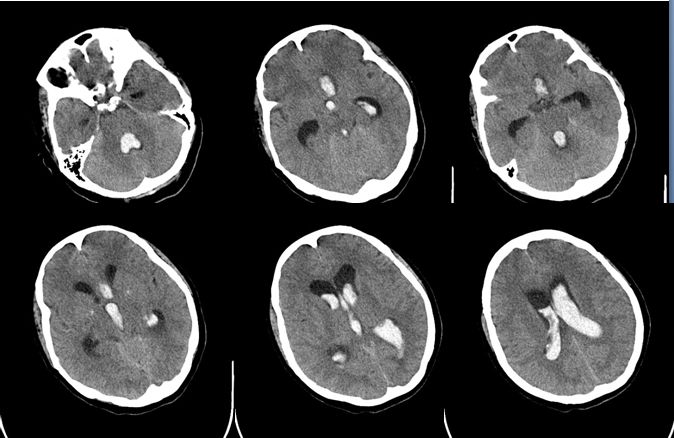

辅查:CT左额叶见大小21mm×11mm血肿,脑室系统积血

2018年2月13日 CT

钻孔引流术后CT

3-18 CT —脑积水